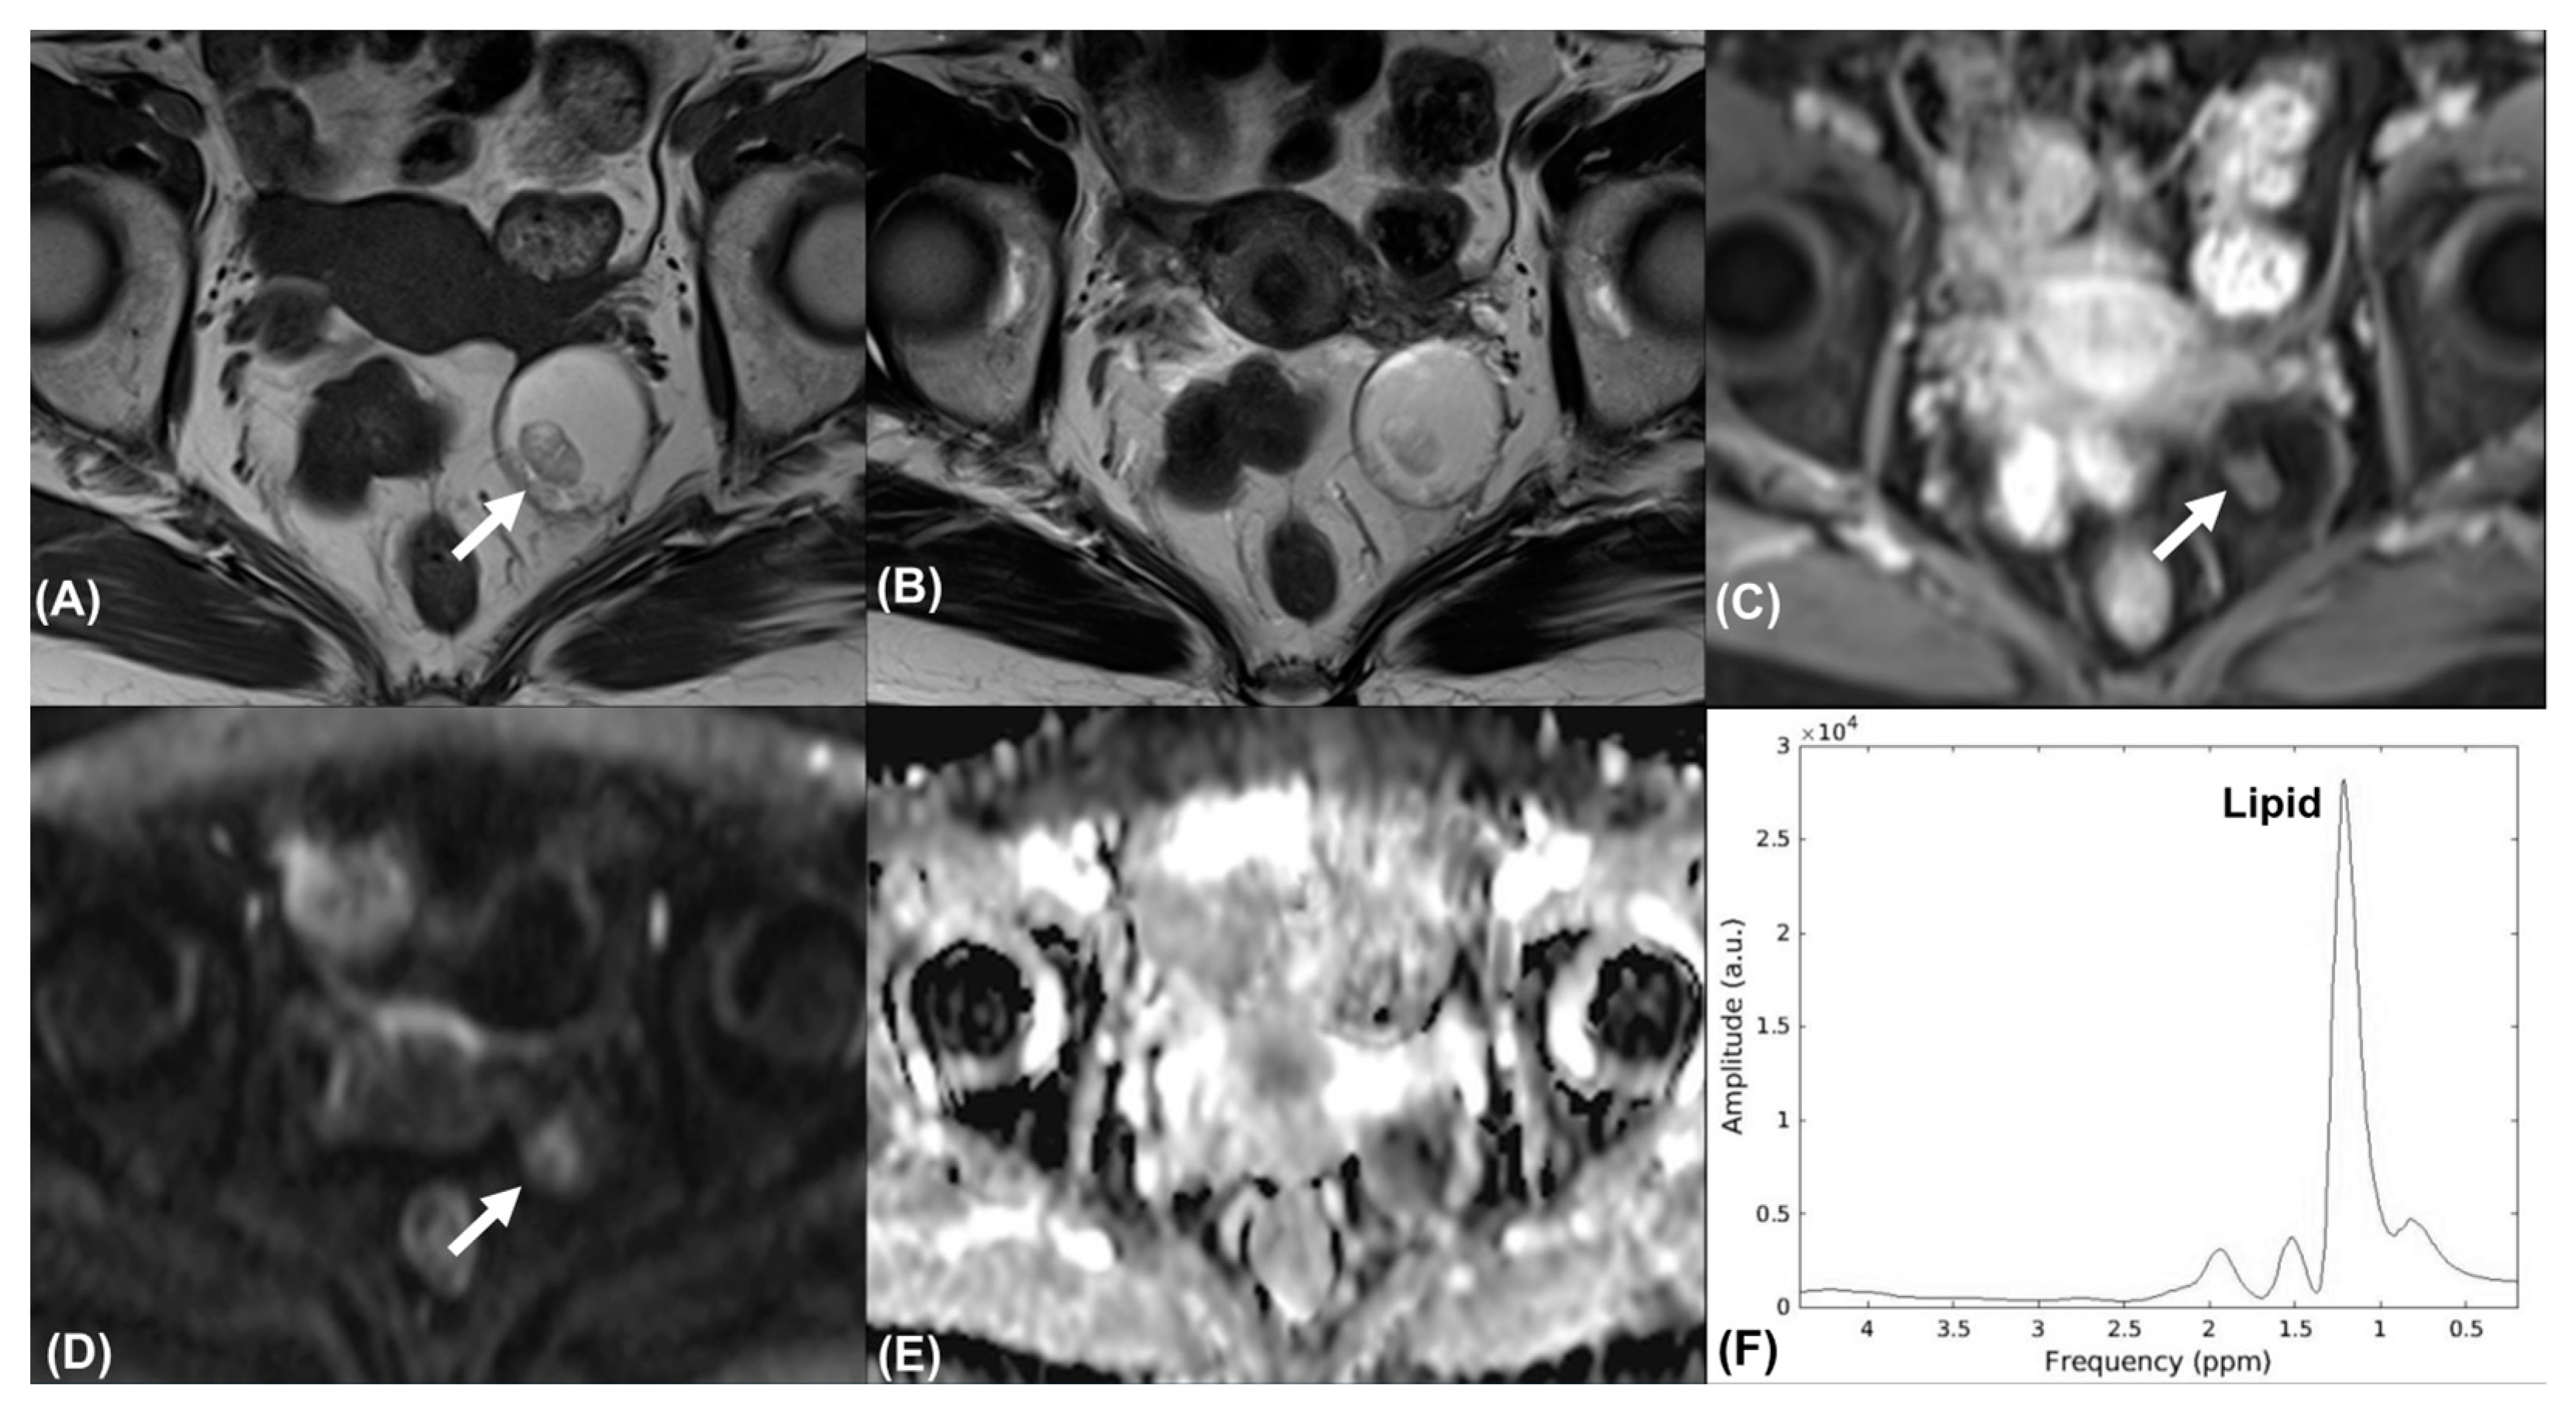

Figure 2.

Mature cystic teratoma in a 67-year-old woman. Axial (A) T1-weighted, (B) T2-weighted, and (C) contrast-enhanced T1-weighted MR images show a left adnexal cystic mass with fatty content. Axial (D) high-b-value DW image (b = 1000 s/mm2) and (E) ADC map demonstrated mild restricted diffusion of the solid nodule (arrow). The tumor was classified as an O-RADS 3 lesion. (F) MR spectroscopy depicts prominent resonances corresponding to lipids (demonstrated using the FID-A toolkit [16]).